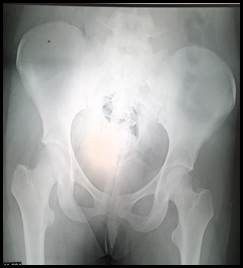

Se realizó un control clínico-radiográfico seriado hasta los 24 meses de evolución, la paciente se encuentra sin dolor durante la marcha, movilidad completa en todos los ejes de movimiento y sin alteraciones radiológicas a nivel de la cabeza femoral (Figura 5 a y Figura 5 b ).

Figura 5a:  Radiografía frente de pelvis, 24 meses de evolución

Figura 5b:  Radiografía frente cadera izquierda, 24 meses de evolución. Sin cambios radiográficos a nivel de cabeza femoral.